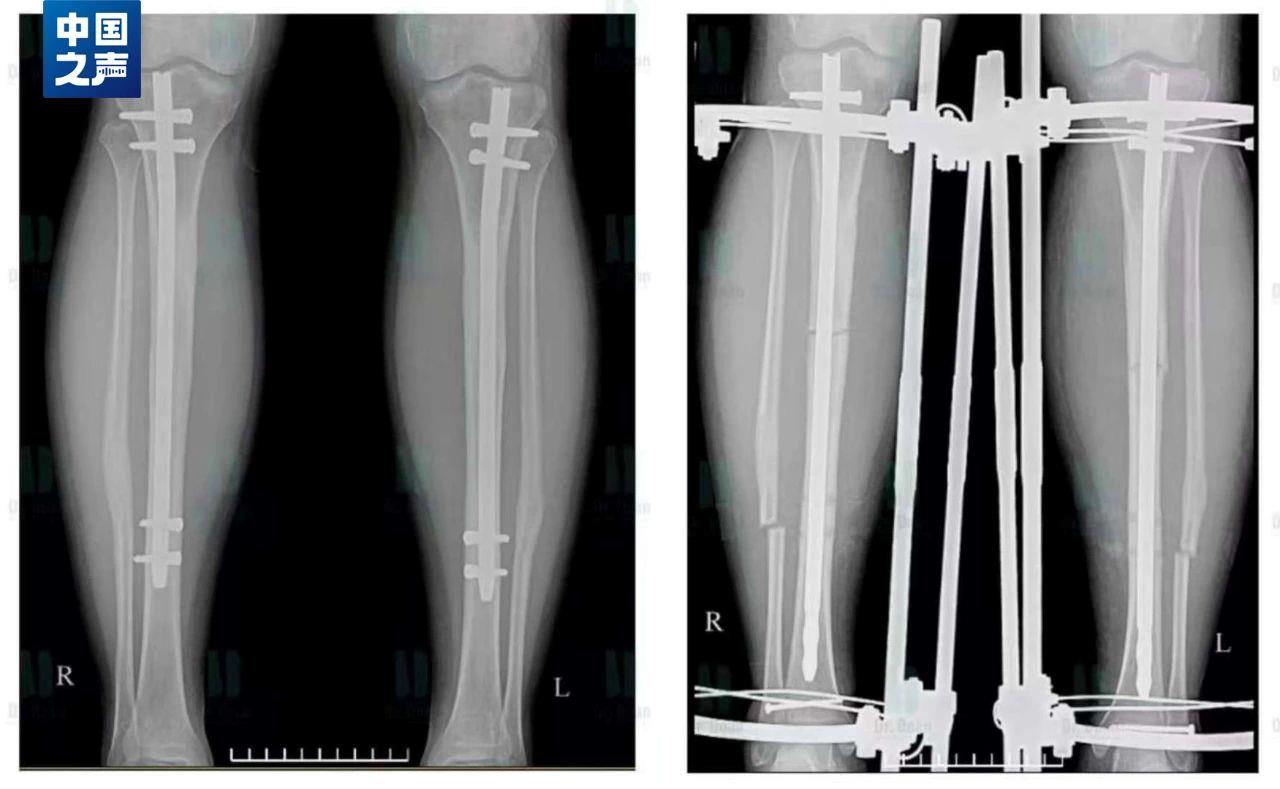

“斷骨增高術”的原理是使用骨科截骨術,在小腿或大腿把已經閉合的骨生長線重新“打開”,並在體外安裝一種具有牽伸作用的肢體延長器,根據每個人的組織再生能力和特點,每天以0.5毫米到1毫米的速度將肢體緩慢延長。而延長的方法就是使用工具旋轉肢體延長器,起到牽引拉長的作用。我國嚴令禁止健康人進行這一危險手術。

實施“斷骨增高術”後拍攝的X光片,鋼釘直接釘進腿骨當中,腿周圍還增加了一圈固定設備起牽引作用。